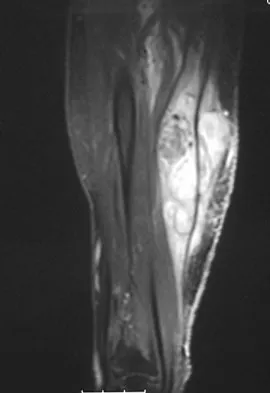

Question 61

A 16-year-old football player sustains a direct blow to the anterior aspect of his flexed right knee. Examination reveals a contusion over the anterior tibial tubercle and a small effusion. MRI scans are shown in Figures 33a through 33c. What is the most likely diagnosis?

Explanation

The MRI scans show disruption of the fibers of the PCL. Patients sustaining an isolated acute PCL injury can present with only minimal discomfort and have full range of motion. When examination reveals a contusion over the tibial tubercle and discomfort with the posterior drawer examination, with or without instability, a possible injury to the PCL should be considered. In acute injuries, the reported accuracy of MRI imaging for diagnosing PCL tears ranges from 96% to 100%. Resnick D, Kang HS: Internal Derangement of Joints: Emphasis on MRI Imaging. Philadelphia, PA, WB Saunders, 1997, pp 699-700. Harner CD, Hoher J: Evaluation and treatment of posterior cruciate ligament injuries. Am J Sports Med 1998;26:471-482.